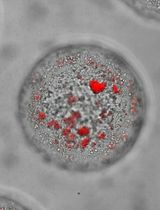

Due to cell heterogeneity, the differences among individual cells are averaged out in bulk analysis methods, especially in the analysis of primary tumor biopsy samples from patients. To deeply understand the cell-to-cell variation in a primary tumor, single-cell culture and analysis with limited amount of cells are in high demand. Microfluidics has been an optimum platform to address the issue given its small reaction volume requirements. Digital microfluidics, which utilizes an electric signal to manipulate individual droplets has shown promise in cell-culture with easy controls. In this work, we realize single cell trapping on digital microfluidic platform by fabricating 3D microstructures on-chip to form semi-closed micro-wells. With this design, 20% of 30 x 30 array can be occupied by isolated single cells. We also use a low evaporation silicon oil and a fluorinated surfactant to lower the droplet actuation voltage and prevent the drop from evaporation, while allowing cell respiration during the long term of culture (24 h). The main steps for single cell trapping on digital microfluidics, as illustrated in this protocol, include 3D microstructures design, 3D microstructures construction on chip and oil film with surfactant for single cell trapping on chip.

In our recent work, we developed a single cell culture method for primary tumor drug screening based on microfabrication and digital microfluidic technologies (Zhai et al., 2020). In the work, 3D microstructures were engineered on digital microfluidic chips for single-cell isolation and long-time culture. With novel combination of medium oil and additives, the droplet actuation voltage was lowered to 36 V, 4 times lower than normally used. Following, breast cancer drug screening was run on-chip with the designed microstructures showing consistent results as in conventional 96-well plates.